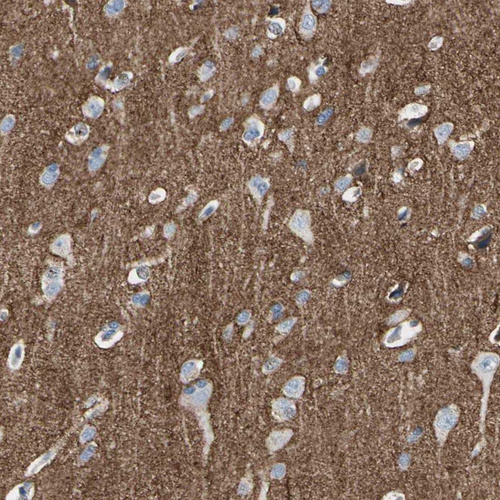

Immunohistochemistry analysis in human cerebral cortex and pancreas tissues using HPA008832 antibody. Corresponding NFASC RNA-seq data are presented for the same tissues.